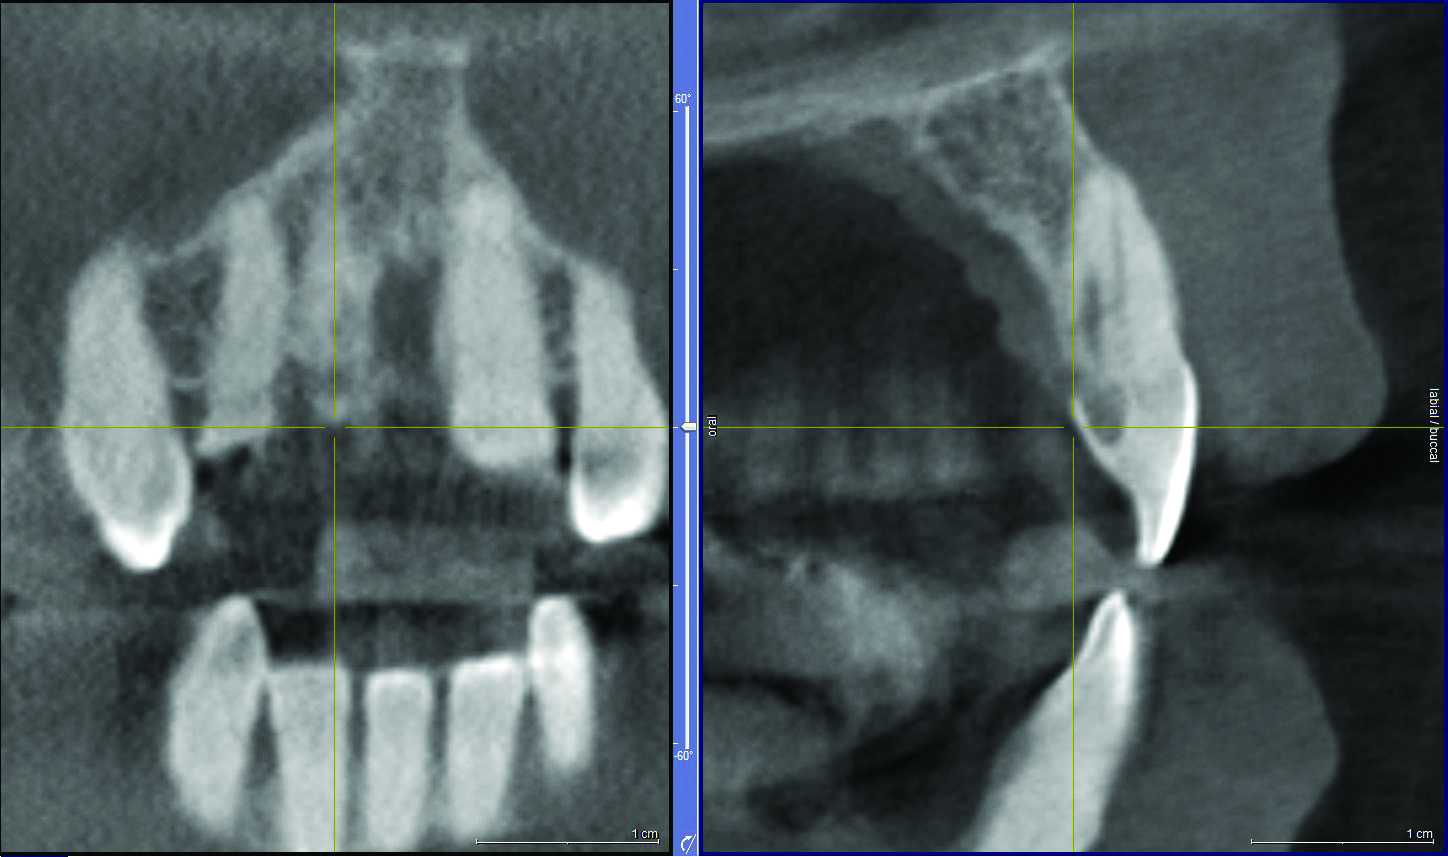

A 57-year-old female was referred to the author’s intramural practice at the University of Iowa College of Dentistry for evaluation of a visually evident, pink lesion associated with the lingual aspect of tooth No. 8 (Figure 1). The patient had no symptoms at the time of the examination. The periodontal status was normal, with isolated areas of facial mucogingival recession (Figure 2). Percussion testing of the maxillary sextant revealed ankylosis of tooth No. 8 based on auditory sounding. A diagnostic cone-beam computed tomography (CBCT) scan was performed. The findings pointed to confirmation of a large external cervical resorption lesion (Heithersay Class IV lesion10) associated with tooth No. 8 (Figure 3), leading to a hopeless long-term prognosis.

Fig 3. CBCT scan and cross-sectional view of tooth No. 8, demonstrating invasive cervical resorption.

Figure 3